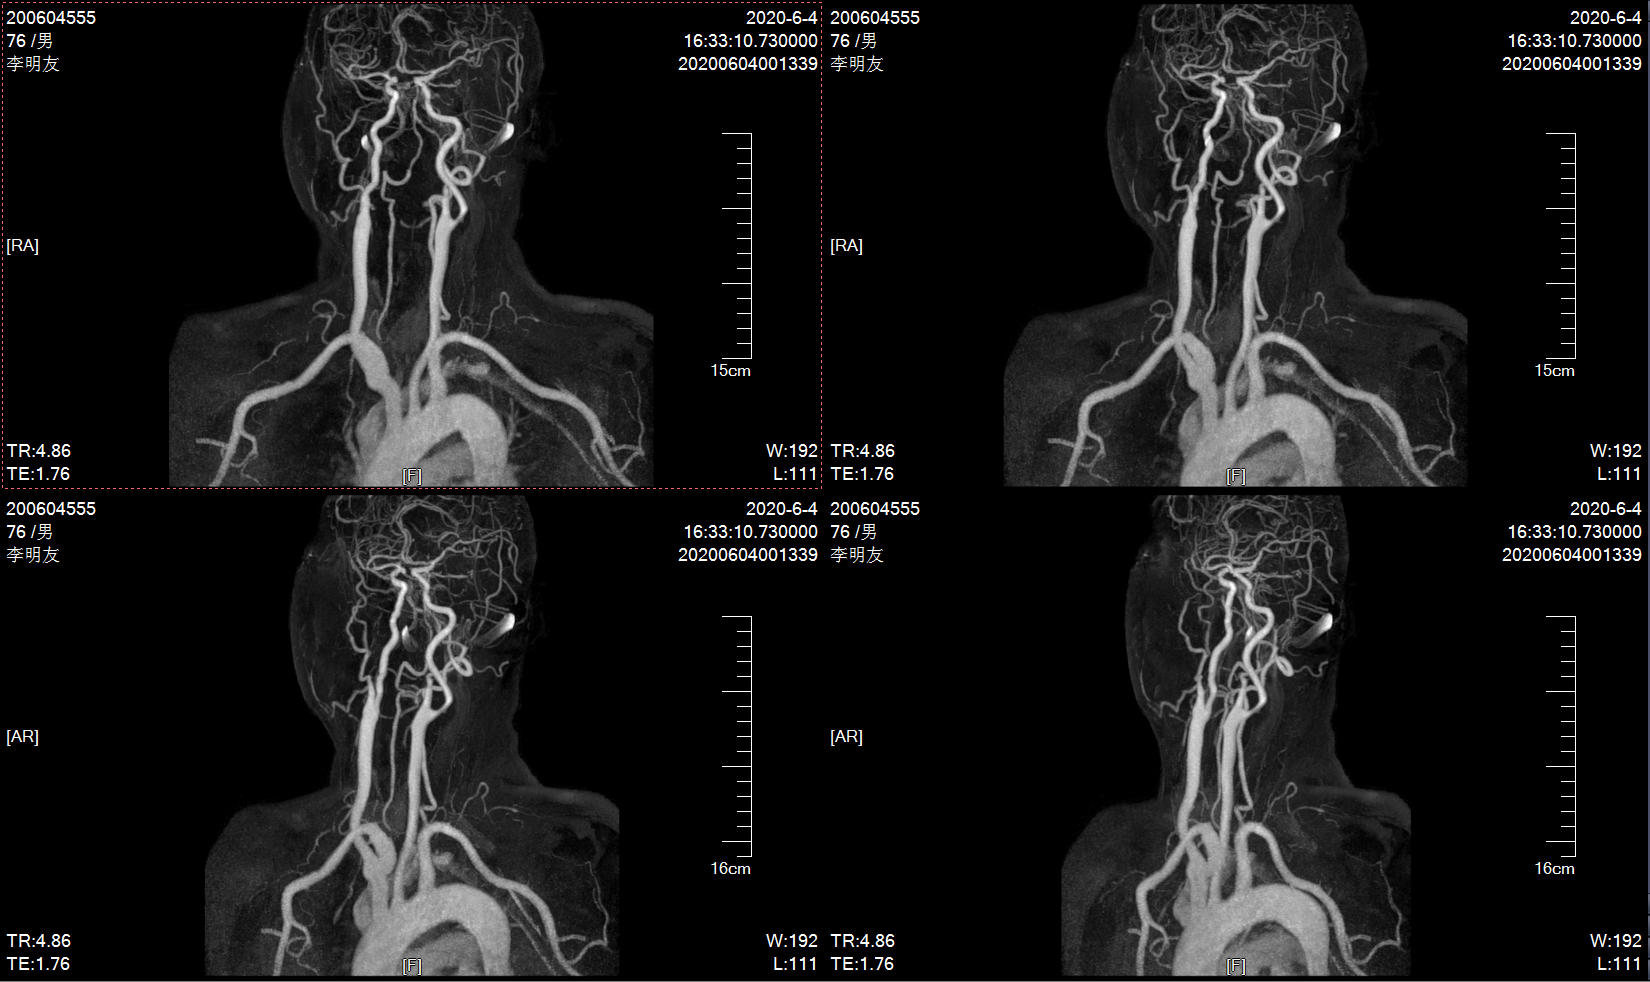

10个月前MRA示左侧颈内动脉轻度狭窄